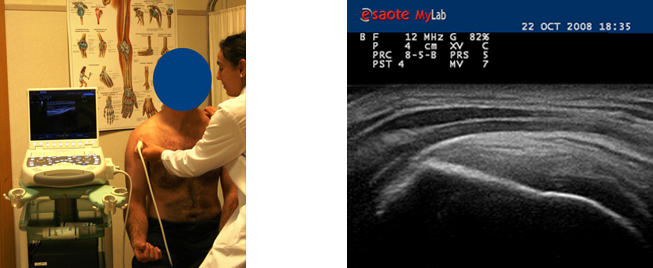

El magneto posee una amplia apertura en los cuatro costados, lo que permite realizar estudios dinámicos de las articulaciones (hombro, rodilla, tobillo, etc) e incluso procedimientos intervencionistas (punciones estereotáxicas, etc).